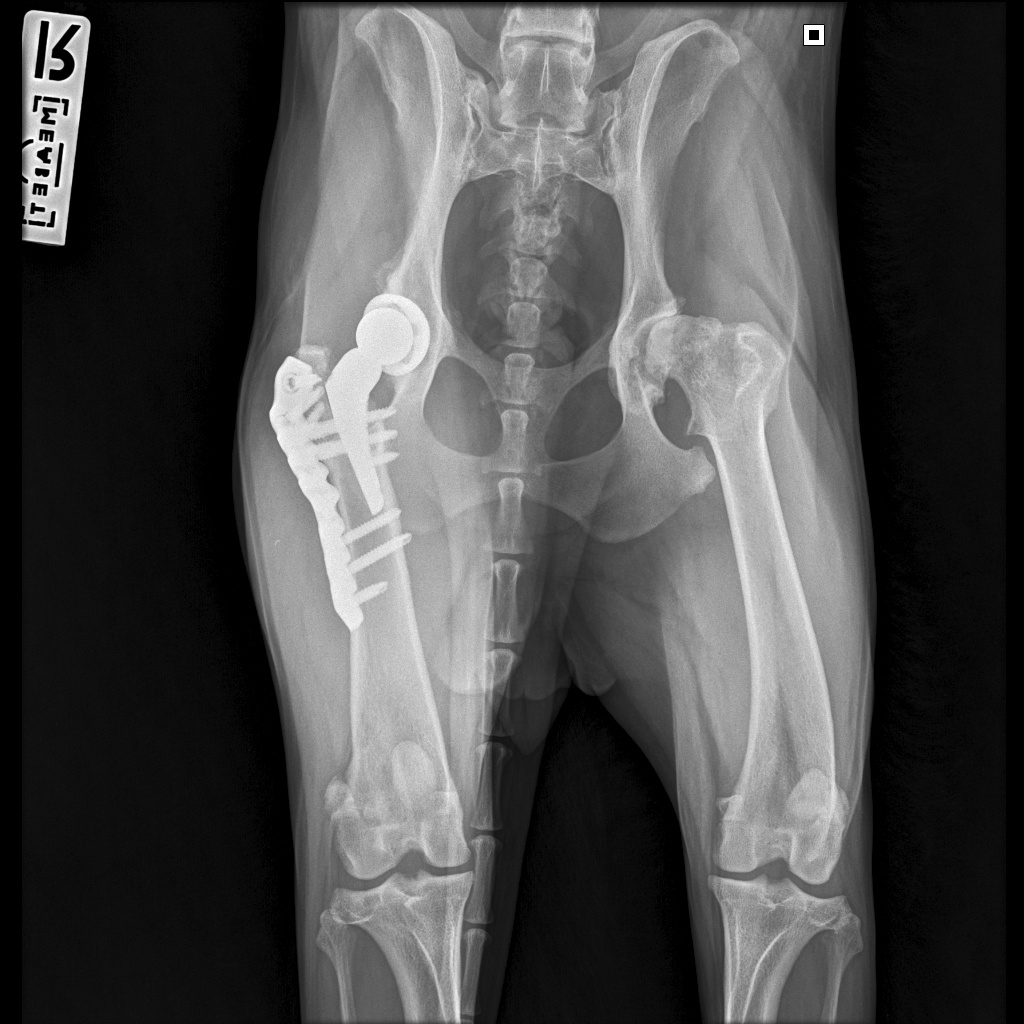

18.08.2025 мы съездили на контрольный рентген. Можно было сделать рентген и в любой ближайшей клинике, но мы предпочли не рисковать. Во-первых, делать снимки нужно было в каких-то особенных проекциях, на которых виден процесс приживления, а, во-вторых, для такого рентгена требовался наркоз. Потому мы решили не искать легких путей и сразу сделать там, где гарантированно все получится в лучшем виде. Так что записались мы в Медвет в Троицке и покатили к 9 утра.

Далее стандартная процедура: разговор с доктором о самочувствии собаки и наличии жалоб, осмотр анестезиологом и Басю забрали. Где-то через час нам вернули ее уже полностью отошедшую от наркоза, сказали, что все у нас хорошо, ограничения с нас сняты и мы можем быть свободны.

Вот как теперь выглядит ее внутренний мир